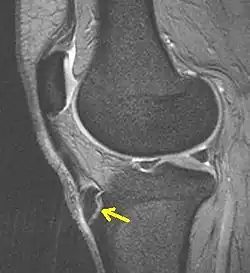

Seitliche Kernspintomografie. Beachte das abgelöste Knochenstück (Pfeil) am Schienbein

Eine Bildgebung kommt bei atypischer Symptomatik in Betracht, dann je nach Fragestellung und Differentialdiagnose Sonographie des Sehnenansatzes (DD:Bursitis, Abszess), eine Röntgenaufnahme seitlich oder selten eine Kernspintomographie. Diagnostische Kriterien sind dann Fragmentation der Tuberositas, Auftreibung der ansetzenden Sehne, Weichteilödem sowie im MRT angrenzende Ödeme in der Tibia.